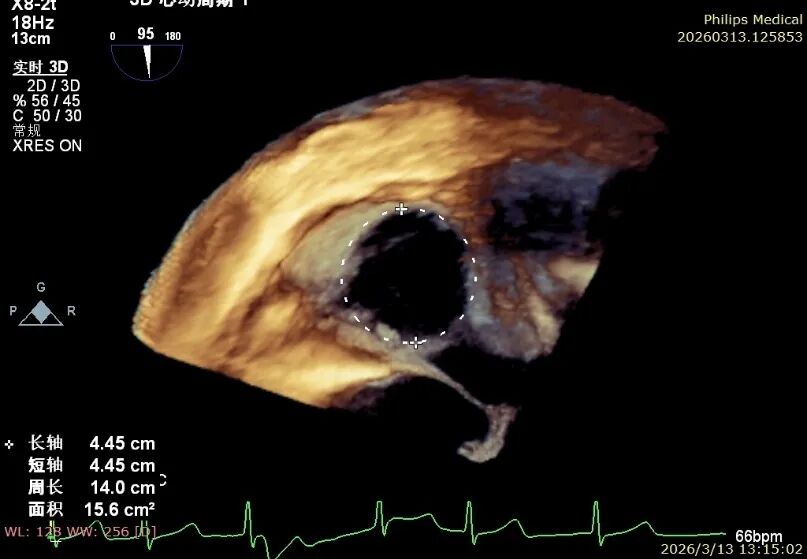

Comparison of Tricuspid Annular Area After Annuloplasty

Preoperative tricuspid annular area: 15.6 cm²